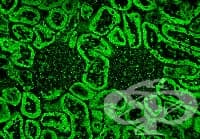

АКЦЕНТИ ОТ РУБРИКА ПАТОМОРФОЛОГИЯ - ЦИТОЛОГИЧНО, ХИСТОЛОГИЧНО, ИМУНОХИСТОХИМИЧНО, ИМУНОФЛУОРЕСЦЕНТНО И ЕЛЕКТРОННО-МИКРОСКОПСКО ИЗСЛЕДВАНЕ

Всички

ВСИЧКИ СТАТИИ